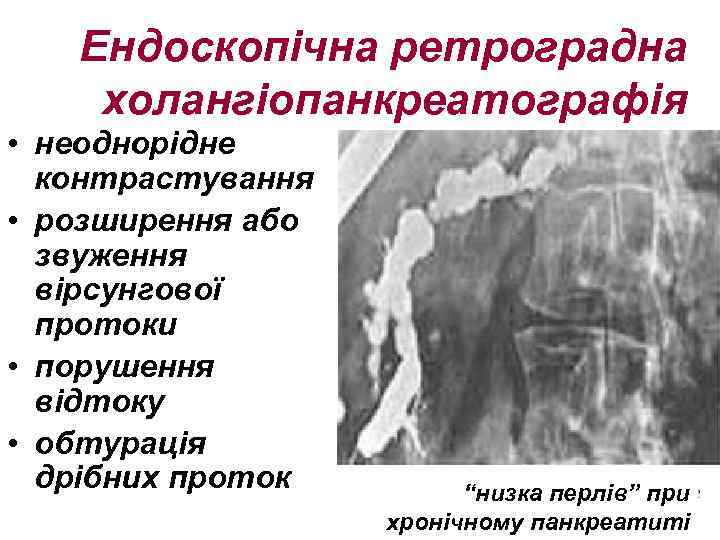

Ендоскопічна ретроградна холангіопанкреатографія • неоднорідне контрастування • розширення або звуження вірсунгової протоки • порушення відтоку • обтурація дрібних проток “низка перлів” при хронічному панкреатиті

Ендоскопічна ретроградна холангіопанкреатографія • неоднорідне контрастування • розширення або звуження вірсунгової протоки • порушення відтоку • обтурація дрібних проток “низка перлів” при хронічному панкреатиті